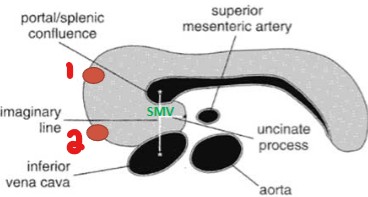

What are the labeled numbers pointing to?

Gastroduodenal artery

Common bile duct